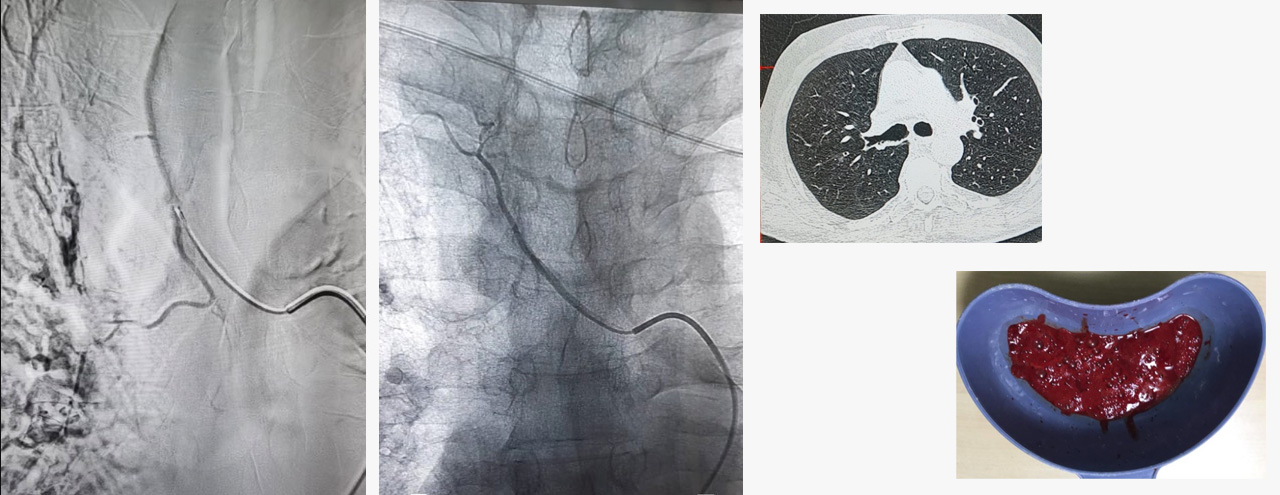

In case of bleeding in the sputum its a blood vessel going to the lung- bronchial artery needs to be addressed and embolised. The procedure is reserved only for life saving conditions as it has small possibility of paraplegia - weakness of both legs , as a complication. Though the chances of this complication is very less, one should be aware about this before opting for this treatment option.